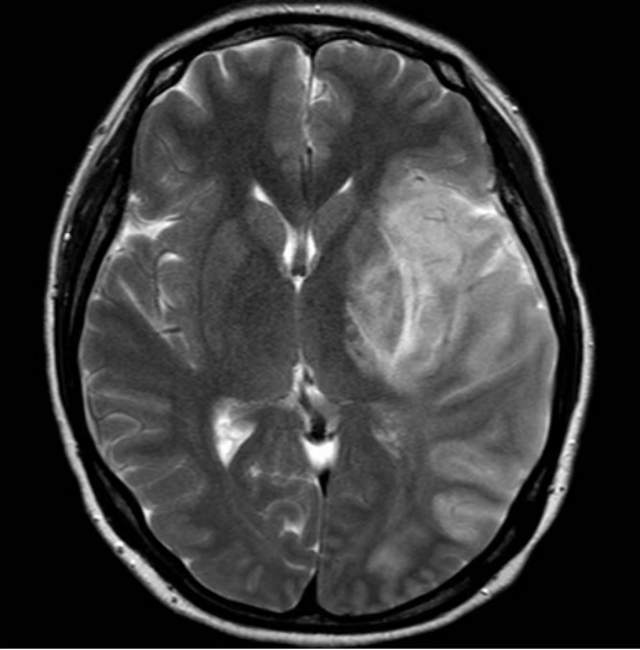

46岁青年女性患者,无高血压和糖尿病病史,突发大面积脑梗塞(图1-2)

遗留右侧肢体残疾,尽管卧床康复3个月,肢体也只能在床上平移,无法抬离床面,完全性失语,不能说话。家属老爸经人介绍辗转收入我科,看看能否得到进一步的改善。第一次晨间病房查房,看到纯朴、善良、苍老的老爸站在床边,向我们不紧不慢的诉说着女儿的病情,年轻秀丽的女儿静静躺在床上,一言不发(完全性失语),想到独生子女家庭在老年突然遭遇失独、残疾等意外后,本是年轻人照顾老年人的季节,现如今却成了白发人弓着背照顾残疾的黑发人,让人心中一阵苍凉和心酸。患者左侧大面积脑梗塞三个月,右侧肢体肌力只有2级,完全性失语;左侧大脑前动脉向左侧大脑中动脉代偿供血,基于上述情况,可能能够做的外科工作并不多,进一步康复的希望也不大。尽管如此,我们还是认真的对患者进行了详尽细致的评估,看看能否找到突破点。造影发现患者颈内动脉起始部存在颈动脉蹼(可能是三个月前引起梗塞的原因,图3)